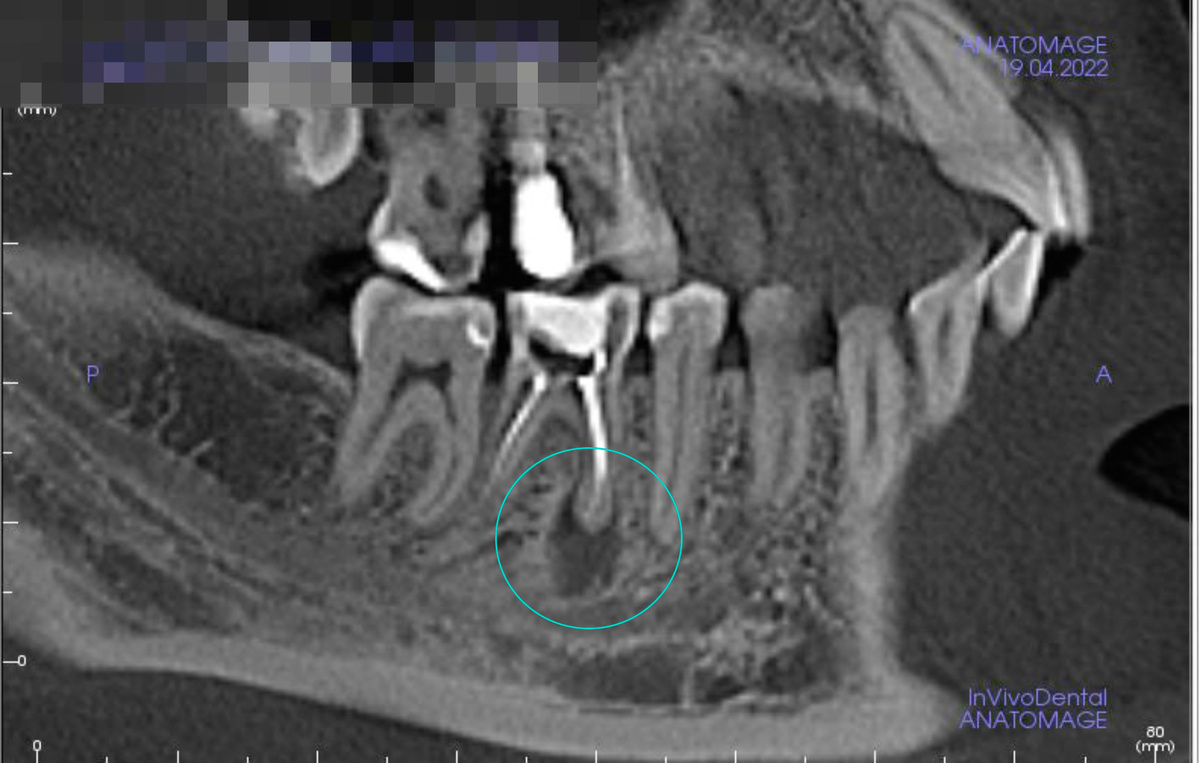

“Киста зуба” – это упрощенное название хронического периодонтита, которая образуется в результате воспаления. Ранее “кисты” часто становились причиной удаления зуба. Сегодня, благодаря современным методам, периодонтит можно лечить, сохраняя зуб. Выбор метода лечения зависит от размера и расположения “кисты”, а также от общего состояния зуба.

— Удалить “кисты” без повреждения зуба

— Вылечить апикальный периодонтит (воспаление на верхушке корней или за верхушкой корней, может возникать вследствие осложненного кариеса)